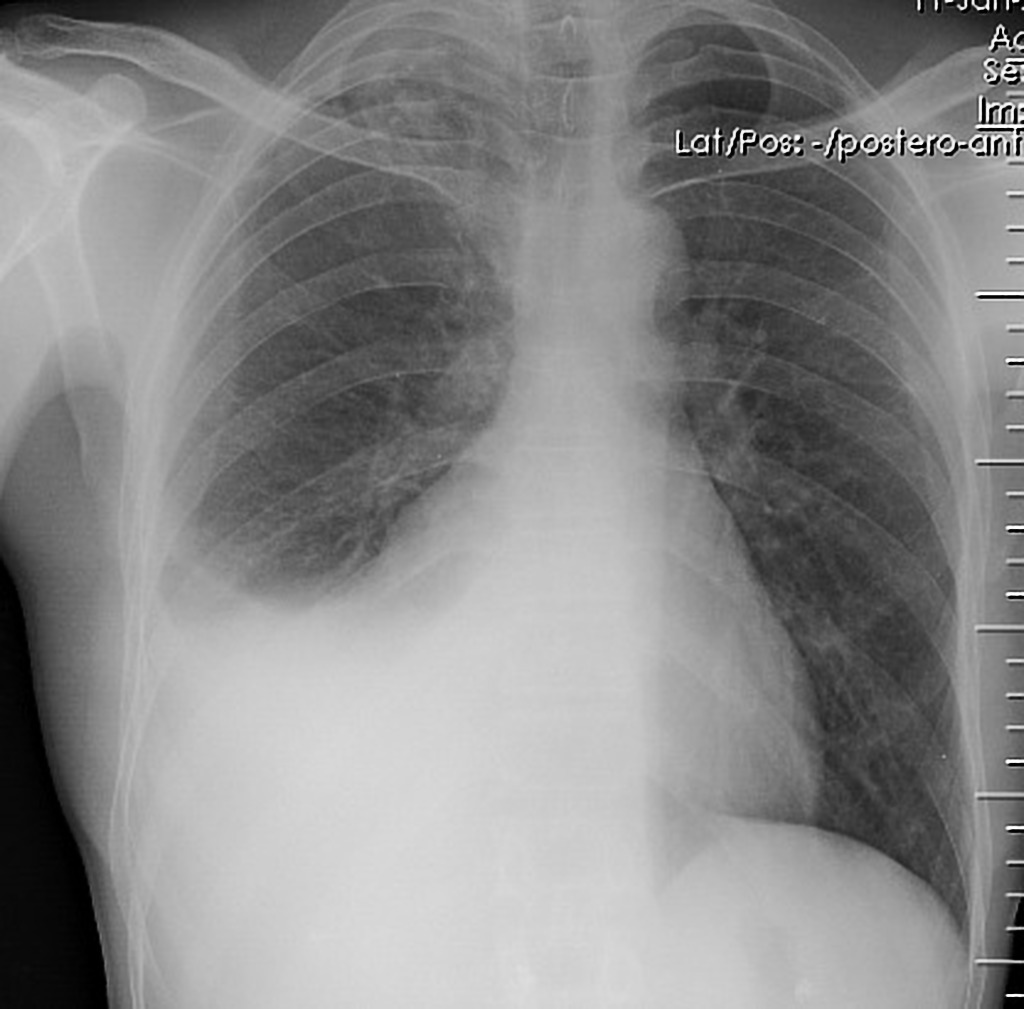

Ix: PA CXR; blunting of costophrenic angle or white-out (large).